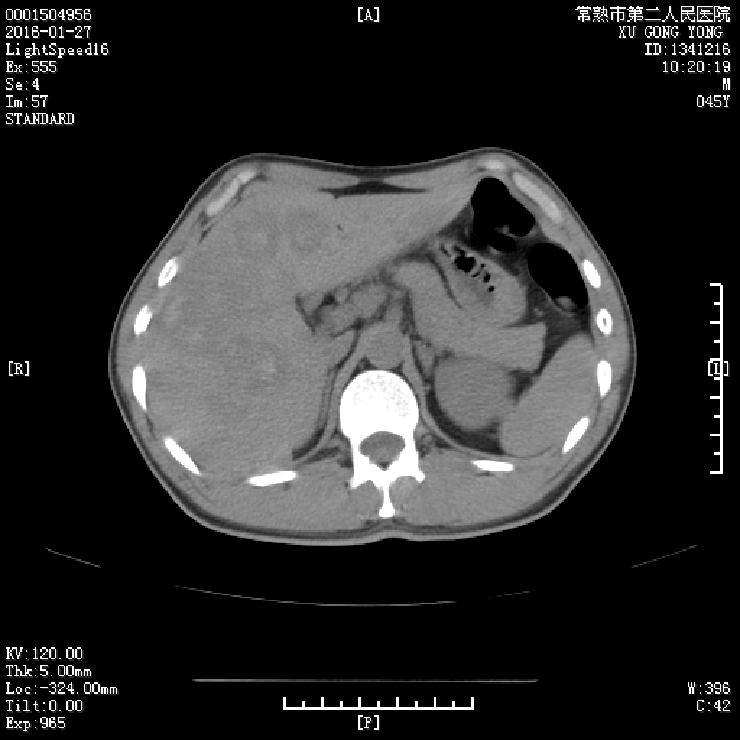

影像学检查:

2016.01.25腹部CT:肝脏多发转移瘤,伴出血可能